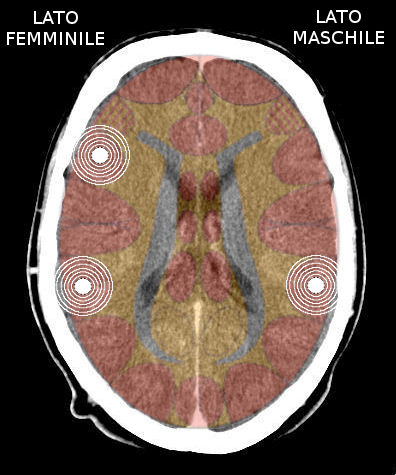

- Requisiti: Si è in costellazione schizofrenica quando due attivazioni colpiscono i due emisferi cerebrali di uno stesso livello:

- le due emiparti del tronco cerebrale;

- i due emisferi cerebellari;

- i due emisferi cerebrali (midollo e/o corteccia).

- NON È COSTELLAZIONE quando due attivazioni interessano due livelli cerebrali differenti, anche se occupano i due emisferi.

Possono esserci due o più costellazioni schizofreniche anche su livelli differenti (ad es. una costellazione corticale e una cerebellare) - I relè cerebrali: In una costellazione si possono avere:

- Un'attivazione in fase attiva ed una in crisi epilettoide

- Entrambe le attivazioni in fase attiva

- Entrambe le attivazioni in crisi epilettoide